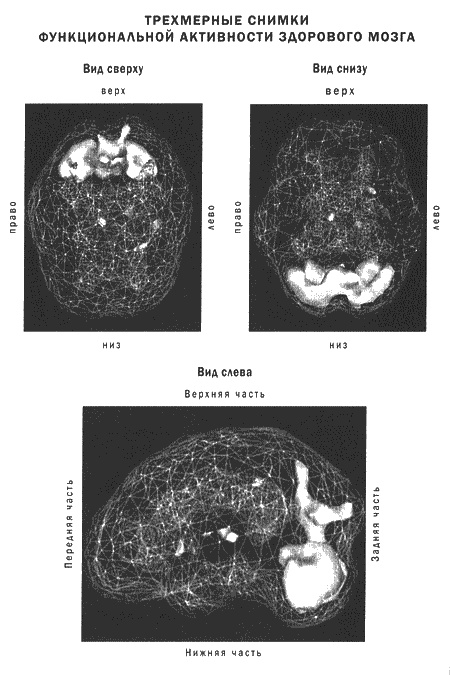

Иллюстрация к книге — Мозг и душа. Новые открытия о влиянии мозга на характер, чувства, эмоции [i_003.jpg]

Томограммы четко показывают, что депрессия сопровождается дисфункциями в эмоциональных и когнитивных центрах мозга.

В трех следующих главах я расскажу о пяти системах мозга, которые связаны со взаимоотношениями, работой и духовным ростом. Это: кора лобных долей, передняя часть поясной извилины, базальные ганглии, височные доли и лимбическая система. Я расскажу о функционировании и возможных проблемах в работе каждой из этих областей, а также об их роли в восприятии добра, зла, любви и в здоровье души. Разумеется, вся теория будет проиллюстрирована историями и сканограммами ОЭКТ.